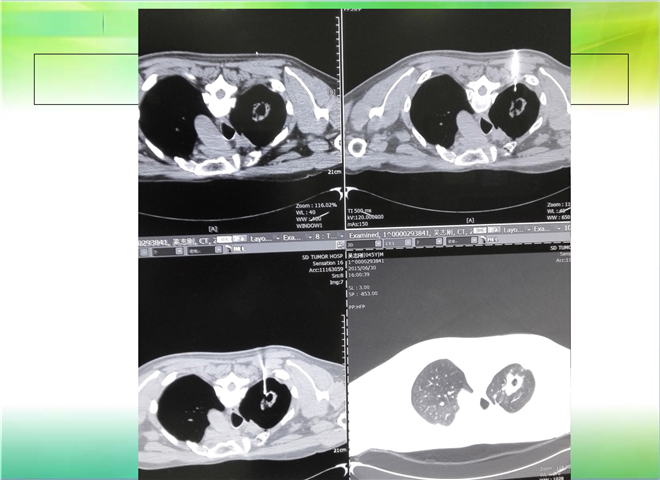

CT引导下穿刺活检术